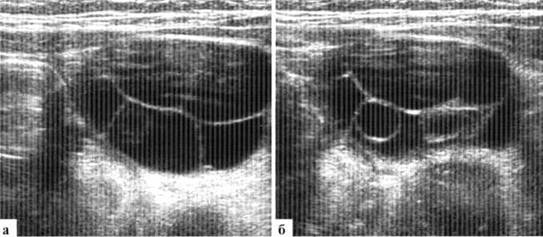

Регулярно определяются доминантные фолликулы. Размеры доминантного фолликула у менструирующих девочек могут в норме достигать 25 мм в диаметре, при этом отчетливо визуализируется сохраненная часть яичника (рис. 1.6). После овуляции ретроматочно иногда определяется минимальное количество жидкости.

Рис. 1.6. Доминантный фолликул в правом яичнике (стрелка) у менструирующей девочки 12 лет

Овуляция может сопровождаться абдоминальным болевым синдромом. Сразу после овуляции доминантный фолликул визуализируется как неправильной формы жидкостное включение в яичнике (рис. 1.7).

Рис. 1.7. Спадение доминантного фолликула правого яичника после овуляции. Ребенок 13 лет